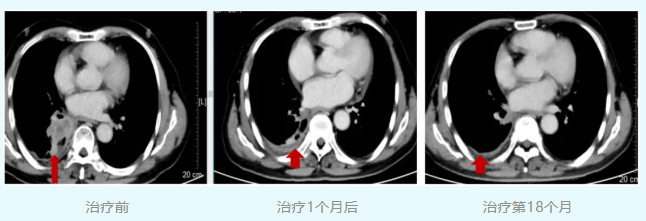

截至日前,患者已接受20周期治疗,过程顺利,无严重不良反应。复查肿瘤明显退缩,疗效PR。现患者活动后气促缓解,肿瘤稳定时间已超18个月。